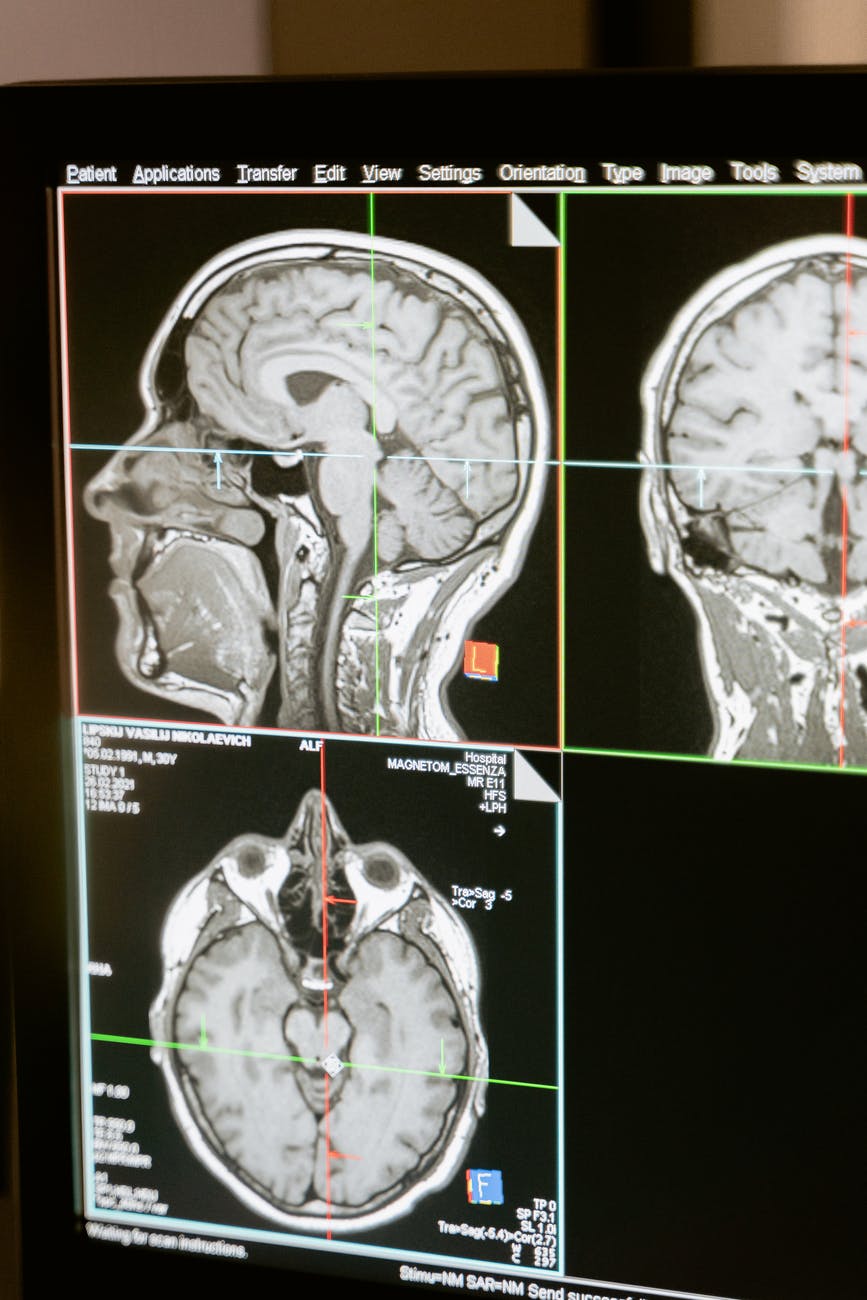

Viele Symptome bei einer Belastung mit EMF, können im Körper lokal zugeordnet werden. Tumore im Gehirn, Kopfschmerzen, Schwindel, Lernstörungen oder auch Schlaflosigkeit und Alzheimer, alle diese Symptome, können vom Ursprung her mit dem Gehirn in Verbindung gebracht werden. Diese Symptome nehmen mehr und mehr zu. Ursache oder Auslöser werden von der Schulmedizin häufig nicht benannt. Lediglich die Funktionsstörung kann relativ genau beschrieben werden. Und so ist auch der Ansatz der Therapie ein funktionaler Ansatz und kein kurativer.

Viele Studien beschränken sich auf die Häufigkeit von Krebserkrankungen. In der Tat konnten inzwischen einige Studien ein vermehrtes Auftreten von Gehirntumoren der Art „Gliom“ bestätigen. Tatsächlich ist es so, dass es bisher keine umfassende Studie im Sinne einer evidenzbasierten, durch klinische Tests und Untersuchungen belastete Studie gibt. Keine (uns bekannte) Studie misst tatsächlich labortechnisch Veränderungen im Blut, Hormonstatus, Atmungskette etc. in Verbindung mit einer Strahlenbelastung durch EMF – im speziellen Mobilfunk. Lediglich ein Wert, den inzwischen die Handyhersteller bekanntgeben müssen, ist ein grober Maßstab dafür, wie der Körper mit Strahlung belastet wird – der SAR – Wert. Was dieser zu bedeuten hat und was er im Kern aussagt, dass Versuchen wir in einem Ergänzungsartikel mit dem Titel „Wenn der Zelle die Luft ausgeht – wie Elektronik die Versorgung der Zelle regelt“, verständlich zu erläutern. Geplant ist dieser Artikel für den 02.08.21